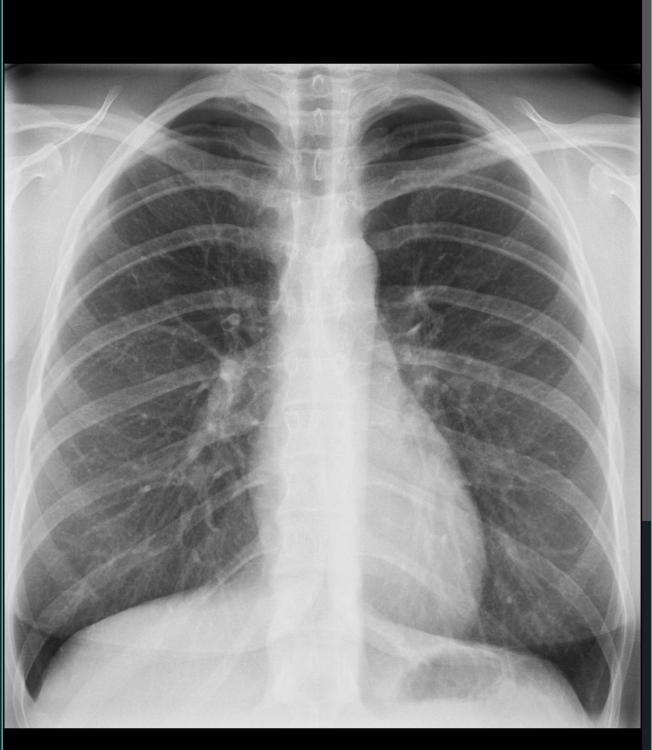

Tok røntgen av lungene idag. Er tidlig i 20 årene. Ser dette normalt ut? Har fibromyalgi så er olaget med bryst og ryggsmerter. Får ikke svar på bildene før neste uke. IMG_5243.thumb.jpeg.7644f0f0126ec0d8d96e4f9958e11e6a.jpegFøler det er små hvite prikker sentralt i brystet:/. Noen radiologer her inne?

Helt normalt røntgenbilde.